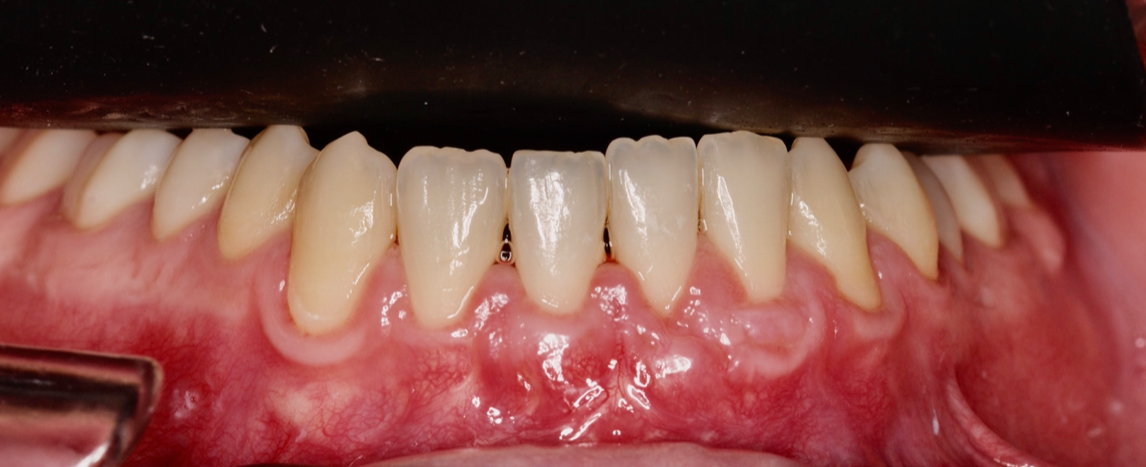

Objetivos periodontales:

- Cobertura radicular en recesión pieza 32.

- Mejora de la sensibilidad

- Estabilidad periodontal mejorando el biotipo gingival y aumento banda encía querantizada

ITC (Injerto tejido conectivo libre desepitelizado de paladar) + tunelización

Fotografías del proceso: